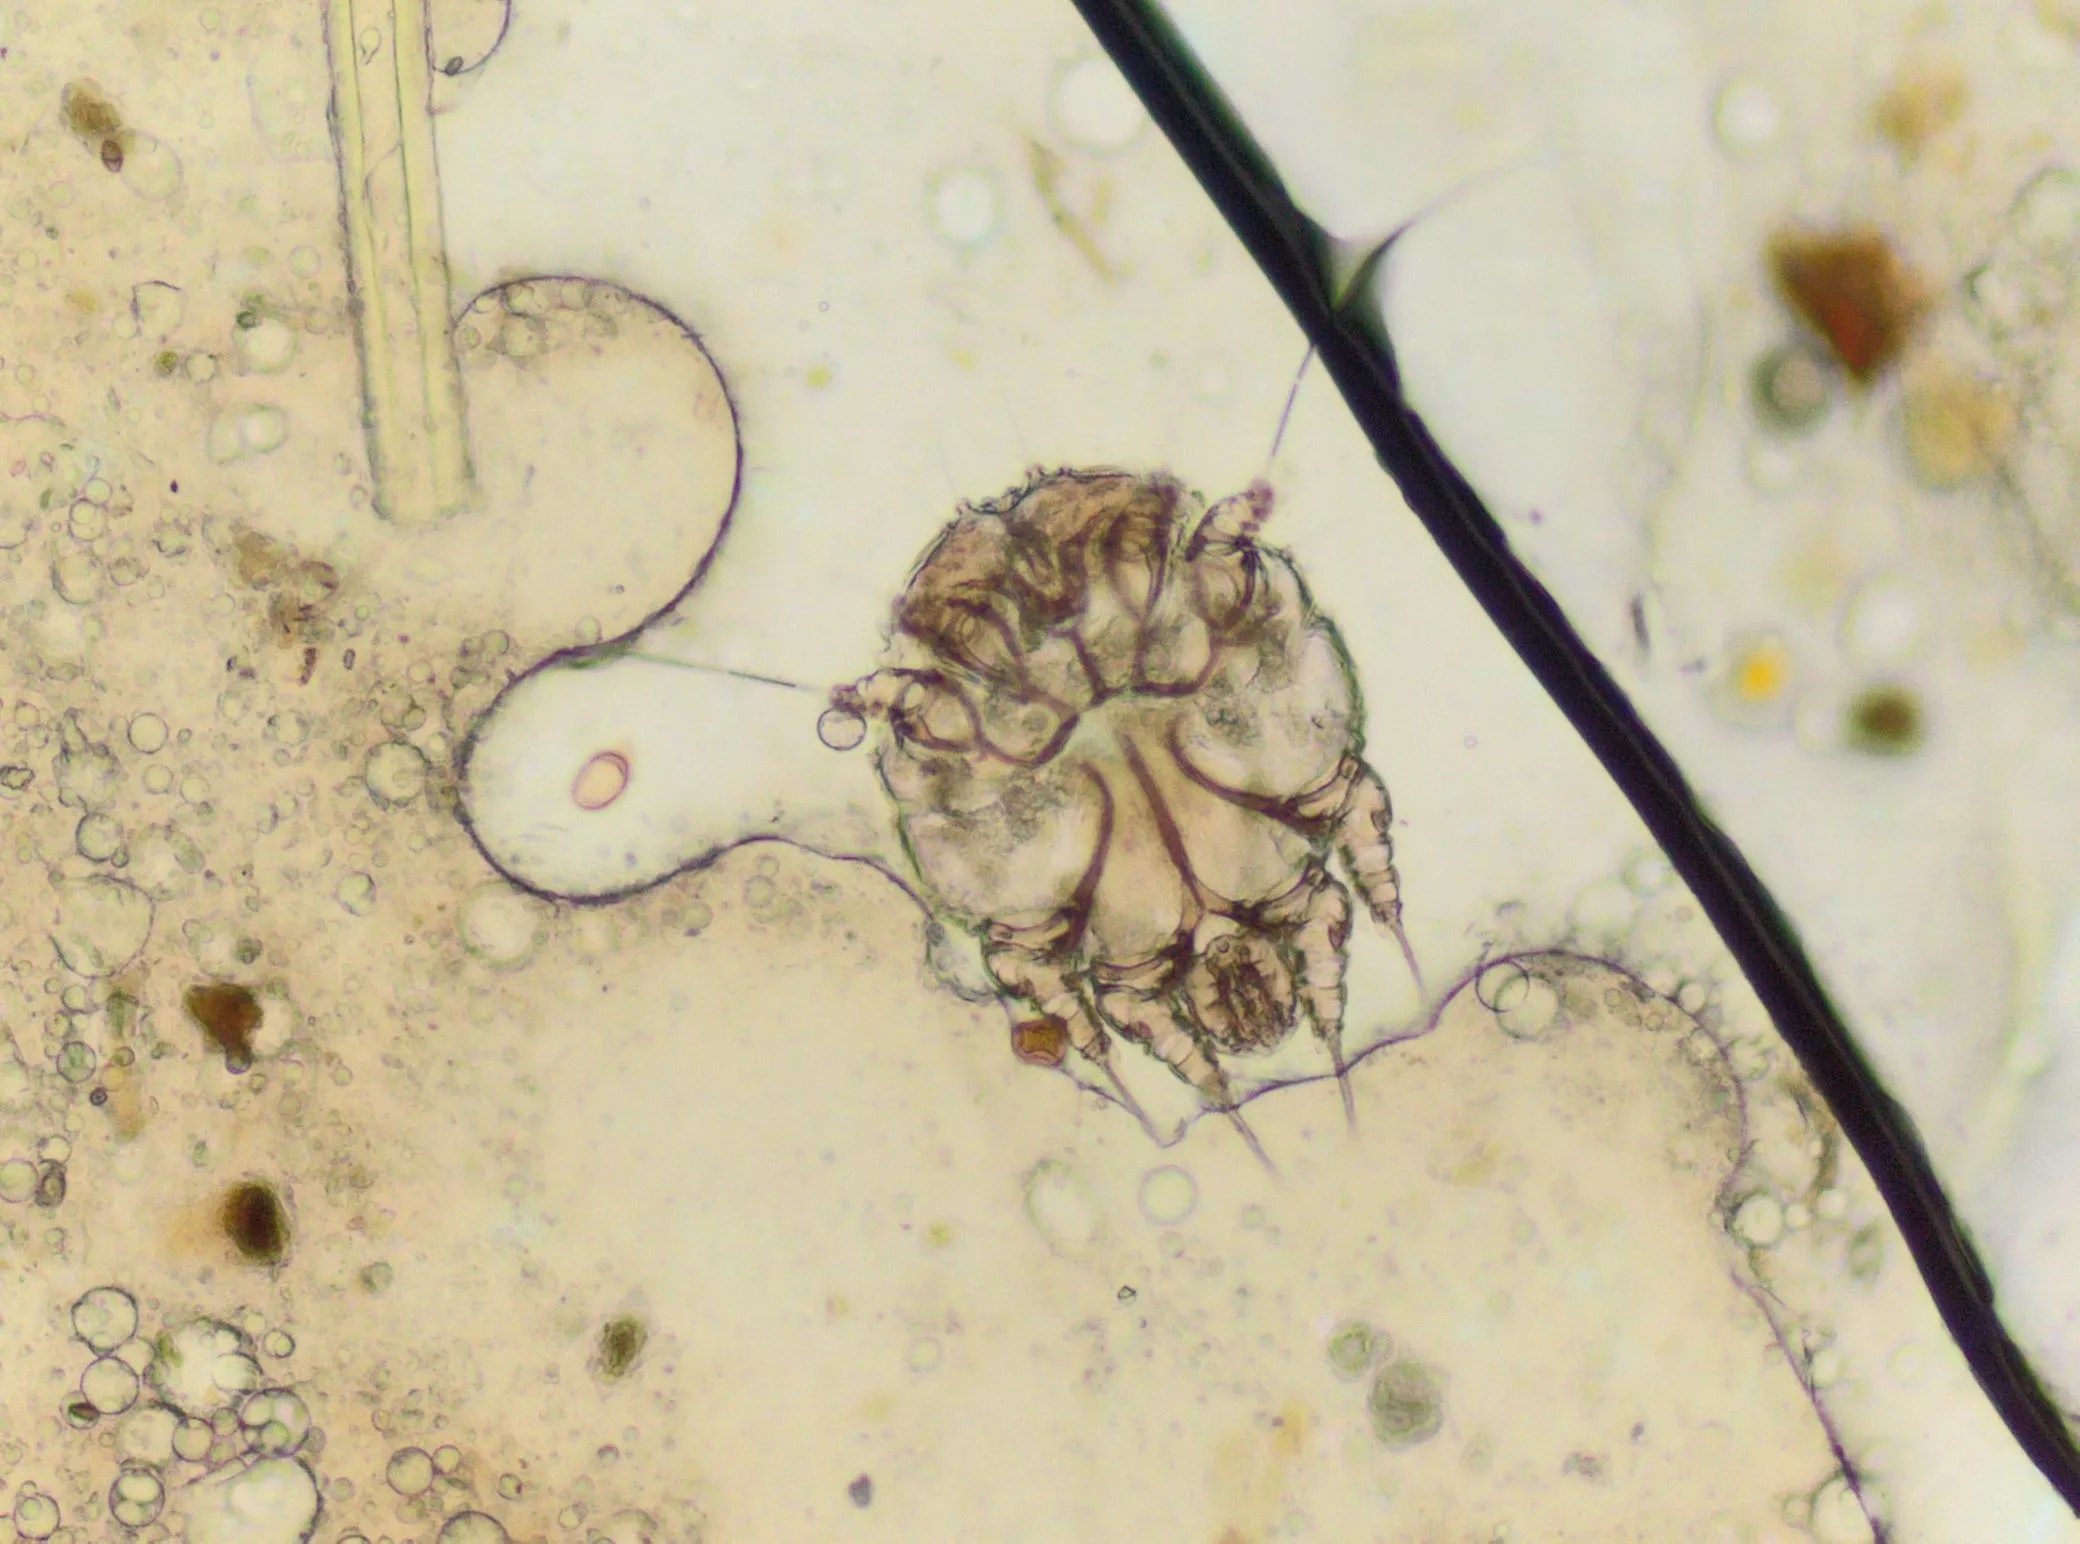

A microscopic view of the mite that causes scabies.

Scabies occurs when a human itch mite burrows into the upper layer of the skin, where it lives and lays its eggs. When a person is infected with scabies for the first time, they can be contagious, even while not displaying symptoms for weeks.

“The most common symptoms of scabies are intense itching and a pimple-like skin rash. The scabies mite usually is spread by direct, prolonged, skin-to-skin contact with a person who has scabies,” according to the Centers for Disease Control and Prevention (CDC). “Prisons are often sites of scabies outbreaks,” the CDC continued.